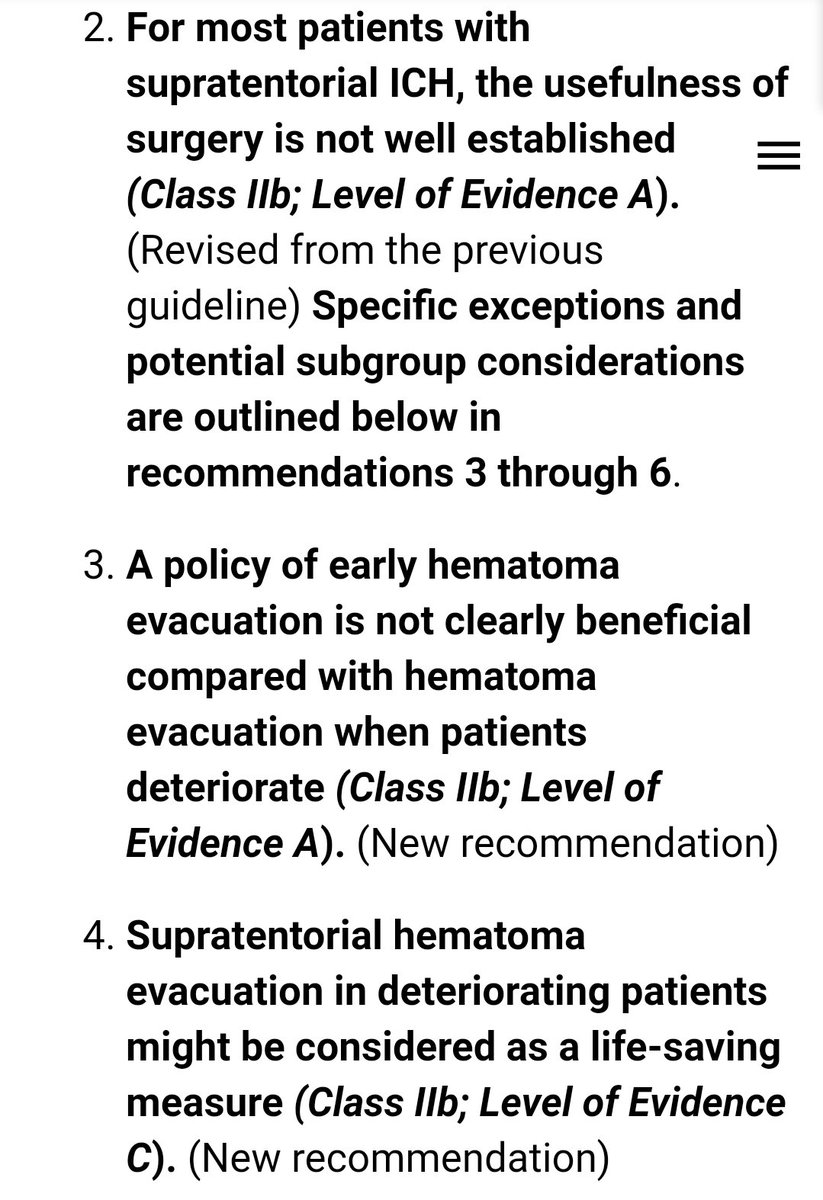

#السكته_الدماغيه_النزفيه

للاطباء🧠

Guidelines for the Management of Spontaneous Intracerebral Hemorrhage

للاطباء🧠

Guidelines for the Management of Spontaneous Intracerebral Hemorrhage